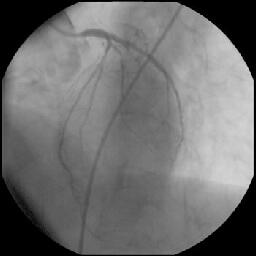

しかし、KBT直前の像(『ChoicePT2.GW.Prolapse』)では屈曲していただけの#9に挿

入したChoice PT2 LSが、KBT時像からは屈曲とともに先端1cm程度が断裂し

(『ChoicePT2.GW.Fracture』)、#9の末梢枝に遺残してしまいました

(『ChoicePT2.Fnl』2枚)。幸い虚血所見がまったくありませんでしたので手技は終

了とし、術後のCK逸脱もなし、翌日お元気に退院されました。

Bostonからの速報では、先端から12mmあたりが切れていると考えられ、であればシェ

イピングリボンよりも手前のシャフトで断裂しているとのことです。USのデータで

は1万本に1本の割合で断裂が生じており、LSよりもMSで高頻度であるとのことでした。